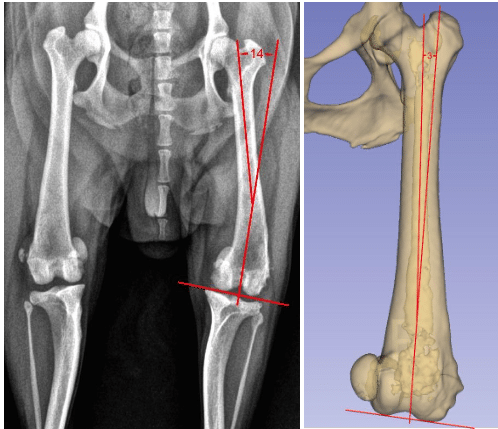

The images to the right are both from the same dog and both show the patella luxated. The radiograph (X-ray) above left, shows about 14 degrees of femoral varus (ie bowlegged curvature to the femur), which is severe enough to warrant consideration of a femoral straightening. However, that measurement from the dog’s X-ray is inaccurate. The 3D reconstruction from the CT scan, which is a superior way for measuring femoral curvature, shows this patient really only has about 3 degrees of excess curvature and does not need the femur straightened.